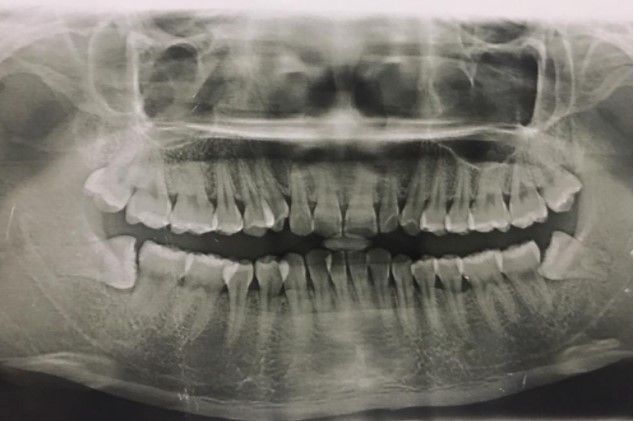

患者,男,38歲。上前牙變色1年,自述上前牙5年前受過外傷,唇側(cè)傾斜,檢查可見左上1牙冠變色,牙冠缺損近1/2,牙髓測試無反應(yīng),X線根尖片顯示患牙無明顯異常,全景片顯示雙側(cè)下頜智齒近中阻生,之前有發(fā)炎化膿病史,目前無咀嚼不適。口腔其余無異常。

檢查情況及X線片見下圖:

(2)檢查見左上1牙冠變色,牙髓測試無反應(yīng),牙冠缺損近1/2,X線片無明顯異常。

非主訴疾病的診斷依據(jù):X線全景片顯示雙側(cè)下頜智齒近中阻生。